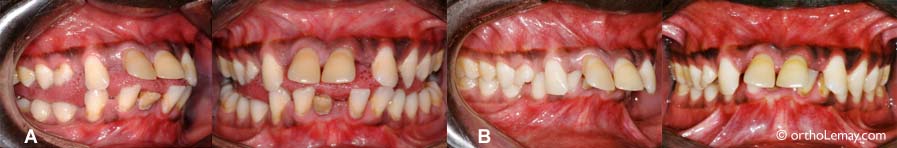

Malgré la gravité de la malocclusion et des problèmes parodontaux affectant ce jeune adulte (24 ans), un traitement d’orthodontie peut être possible. Ceci nécessite une approche inter-disciplinaire et un suivi régulier avec un parodontiste pendant le traitement. La condition parodontale très avancée a complètement détruit l’os autour des racines des incisives centrales inférieures de sorte que ces dents étaient irrécupérables et durent être extraites. Ces photos illustrent le résultat après les corrections orthodontiques.

adulte de 24 ans, le parodonte des dents antérieures présente une perte osseuse importante

Lorsqu’un parodonte est affaibli par la perte de tissus de support, des forces habituellement considérées comme “normales” peuvent devenir trop importantes pour être contenues par la dentition. Ainsi, dans le cas de ce jeune adulte de 24 ans, le parodonte des dents antérieures présente une perte osseuse importante. La langue, déjà “hyperactive” dans cette bouche, constitue maintenant une force trop importante pour que les dents puissent lui résister. Il s’ensuit donc des déplacements dentaires; les dents antérieures basculent vers l’avant et s’espacent. (A) Position de “repos” habituelle; la langue exerce une pression constante contre les dents. (B) Façon de mordre lorsqu’on lui demande de reculer volontairement sa langue et de “forcer” pour fermer ses dents ensemble. Note : La couleur foncée de la gencive est due au fait que cette personne est de race noire. Les résultats du traitement d’orthodontie et de parodontie sont illustrés ci-dessous.